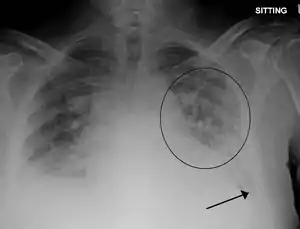

X-Ray showing pulmonary edema

Low oxygen saturation in blood and disturbed arterial blood gas readings support the proposed diagnosis by suggesting a pulmonary shunt. A chest X-ray will show fluid in the alveolar walls, Kerley B lines, increased vascular shadowing in a classical batwing peri-hilum pattern, upper lobe diversion (biased blood flow to the superior parts instead of inferior parts of the lung), and possibly pleural effusions. In contrast, patchy alveolar infiltrates are more typically associated with noncardiogenic edema[2]